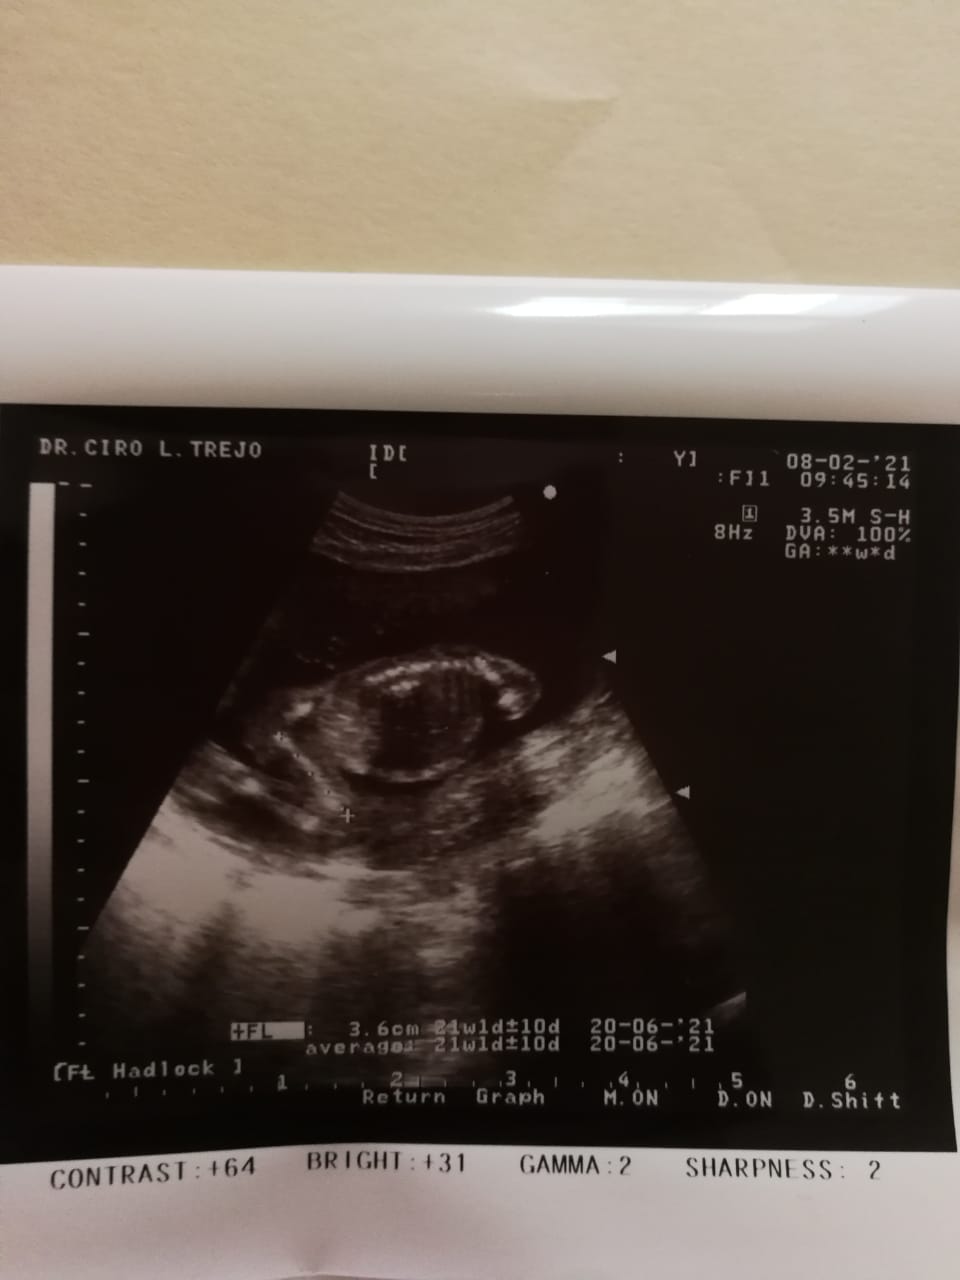

I’ve been pregnant four times. Each time we found out, we were overjoyed—filled with hope and excitement. But that happiness was always cut short. Every single pregnancy ended in miscarriage. The pain is indescribable. Each loss sent me into a deep depression, grieving the baby we had already begun to love. Through it all, my husband has been my rock, holding me up and reminding me not to give up on our dream.